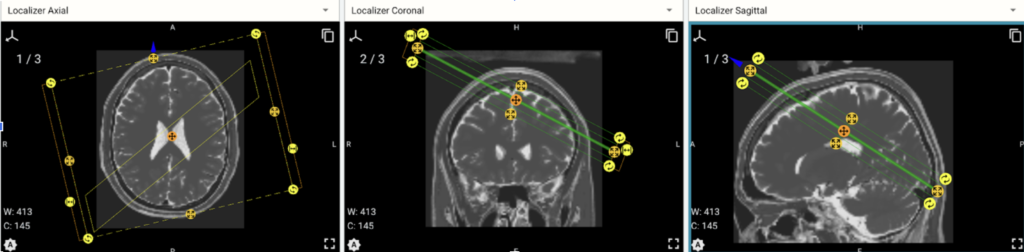

This project was about fixing a mismatch between the orientation of MRI slices before being processed by a Python engine and after that processing.